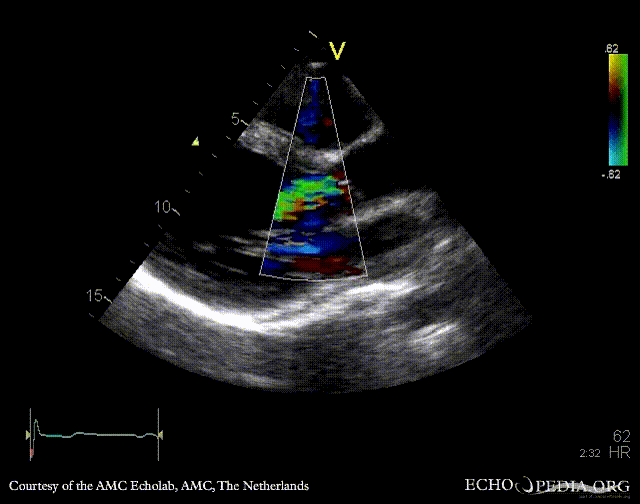

E00341.gif E00342.gif

A5CH: Color Doppler, moderate aortic regurgitation PSAX: bicuspid aortic valve